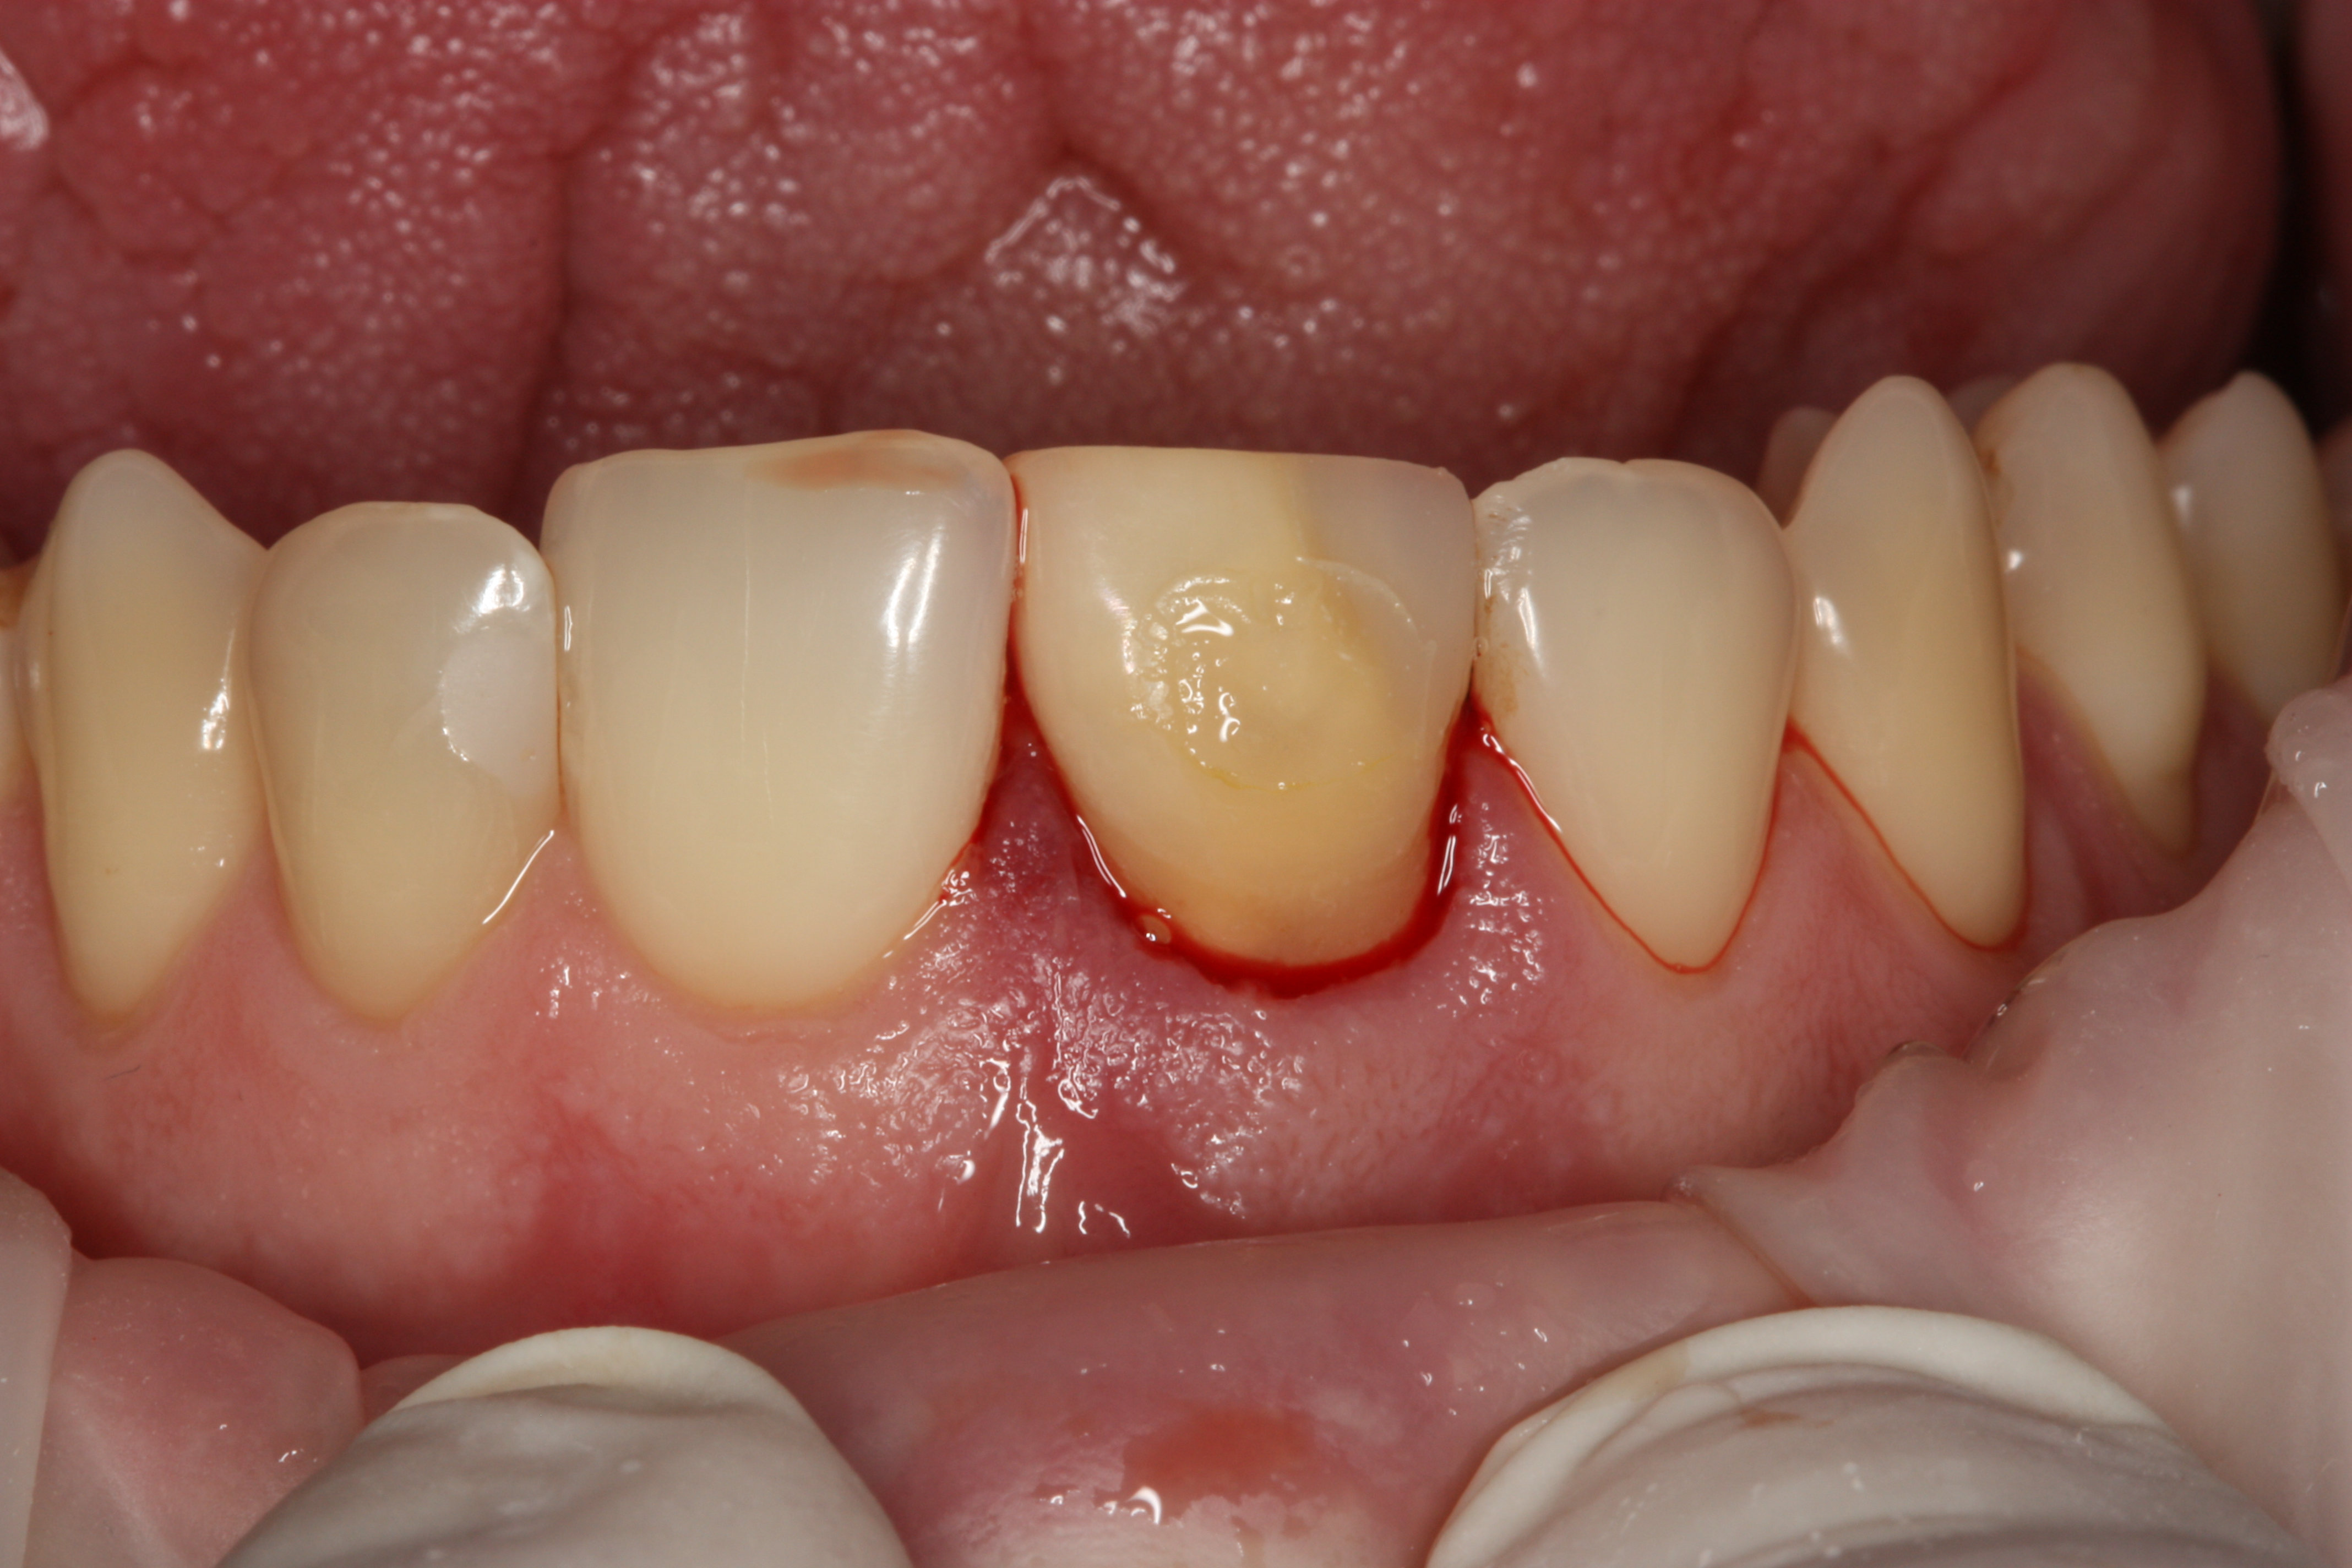

Przykład ekstruzji ortodontycznej za pomocą płytki termoformowalnej i zameczka ortodontycznego: